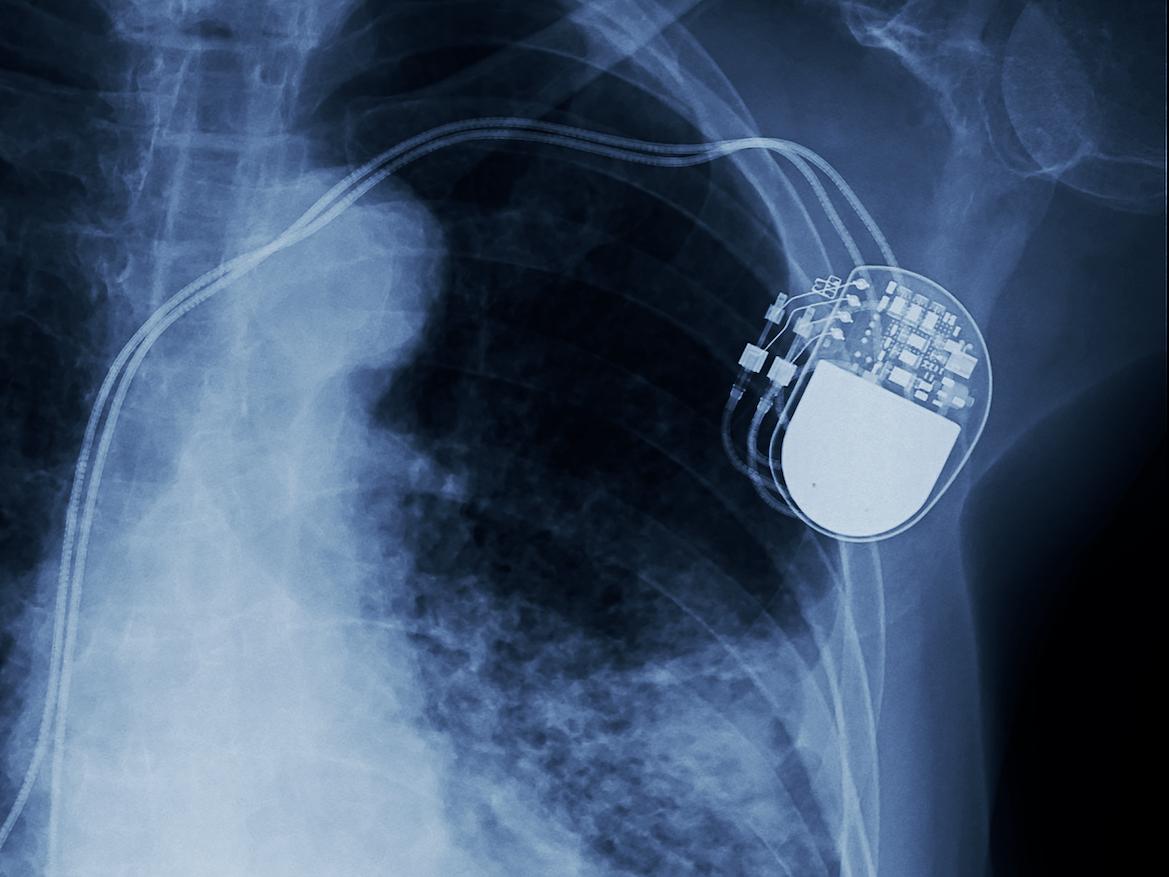

Le stimulateur cardiaque est un appareil qui détecte d’éventuelles troubles du rythme ventriculaire pour les corriger. Le joueur de football danois Christian Eriksen, qui a fait un malaise cardiaque en plein match du championnat d’Europe, va en être équipé. Comme le footballeur de 29 ans, entre 60 000 et 70 000 Français s’en font implanter chaque année. Des chercheurs américains des universités Northwestern et George Washington ont développé le tout premier stimulateur cardiaque transitoire. Présenté le 28 juin dans la revue Nature biotechnology, l’appareil de stimulation fonctionne sans fil, sans batterie et disparaît naturellement dans le corps une fois qu'il n'est plus nécessaire. Il fait 250 microns d'épaisseur, soit 0,025 centimètres, et pèse moins d’un demi-gramme.

Ce nouvel outil représente une alternative pour les patients qui ont besoin d'une stimulation temporaire après une chirurgie cardiaque ou pour ceux qui attendent la pose d’un stimulateur cardiaque permanent. Tous les composants du stimulateur cardiaque transitoire sont biocompatibles et s'absorbent naturellement dans les biofluides corporels pendant cinq à sept semaines, sans nécessiter d’intervention chirurgicale. L’appareil fonctionne en récupérant l'énergie d'une antenne externe distante à l'aide de protocoles de communication en champ proche, la même technologie que celle utilisée dans les smartphones pour les paiements électroniques, pour envoyer des stimulations cardiaques s’il en constate la nécessité.

Des stimulateurs temporaires existent déjà mais le matériel est encombrant et dangereux pour les patients. Pour les installer, après une chirurgie à cœur ouvert, les chirurgiens doivent coudre des électrodes de stimulateur cardiaque temporaires sur le muscle cardiaque. Cela conduit à ce que le patient ait des fils qui sortent de l'avant de la poitrine pour se connecter à un boîtier de stimulation externe qui délivre un courant pour contrôler le rythme cardiaque. Ce modèle fait courir le risque que les sondes puissent s'envelopper de tissu cicatriciel pouvant causer d'autres dommages lorsqu'elles sont retirées, tels qu’une infection, un délogement, des tissus déchirés ou endommagés, des saignements et des caillots sanguins.